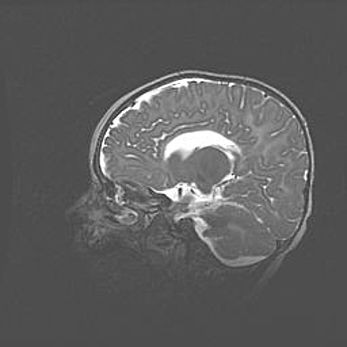

Церебральная ишемия II.

Возраст: 5 дней

Вес: 3400 г

Пол: женский

Окружность головы: 35 см

Срок гестации: 39 недель

Церебральная ишемия – это заболевание, характеризующееся недостаточностью (гипоксией) либо полным прекращением (аноксией) снабжения мозга кислородом по причине закупорки одного или нескольких сосудов. Это приводит к  что метаболическим расстройствам различной степени тяжести в тканях головного мозга, развитию коагуляционных некрозов и гибели нейронов.